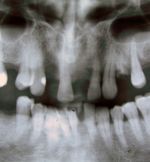

CELTЧастных стоматологических кабинетов и клиник в Москве – множество, в настоящее время более 950-ти только официально зарегистрированных. Большинство из них представляют пункт стоматологической помощи на 1-2, реже 3 кресла, где стоматологические услуги предоставлены терапевтической и ортопедической, иногда хирургической помощью. Стоматологическое отделение МК «ЦЭЛТ» оснащено всем необходимым, включая рентгенологическое и диагностическое оборудование, без которого немыслима качественная стоматологическая помощь >>